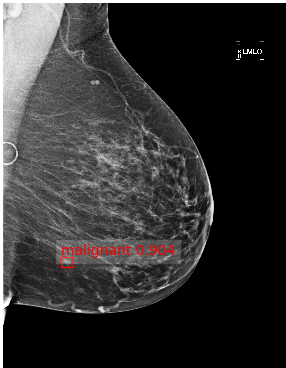

Based on these results, we submitted our final architecture described in Section 2 for testing on the large GH-Validation dataset. In the first sub-challenge, which records the AUC by breast purely on imaging and blinded to demographic information, we achieved AUC=0.879 (standard deviation: 0.00914), see Fig. 2(e), which is 0.005 above the top AUC in the competitive phase of the Challenge. It was also the highest single-model AUC in the collaborative phase, 0.014 below an ensemble of detection models, and higher than all patch-based models. The second sub-challenge is on subject-wise AUC, with access to both images and demographics. Despite ignoring demographics, our architecture gave AUC=0.868, behind only the top score in the competitive phase (a patch-based curriculum-trained model) by 0.006. Twenty-five method descriptions from this phase are available at synapse.org, but details of the collaborative phase, including performance of patch-based models trained on Optimam, is embargoed pending publication by the Challenge. Fig. 2 shows sample outputs from GH.

Refer to caption

Figure 2: (a) True positive prediction (p=0.90𝑝0.90p=0.90 probability of malignancy) of an inconspicuous lesion on a left MLO of a 73 year old woman. (b) True negative (malignancy: p=0.06𝑝0.06p=0.06) for left MLO view of a 66 year old woman. (c) False positive (p=0.78𝑝0.78p=0.78) on left MLO of a 43 year old woman, due to hyper-intense region. (d) False negative (p=0.03𝑝0.03p=0.03) for left CC view of a 61 year old woman. (e) ROC by breast, AUC = 0.879.